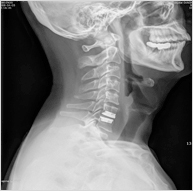

인공디스크치환술

만성 디스크 환자 중 오랜 치료로도 요통이 호전되지 않을 경우 병든 디스크를 모두 제거한 후 인공디스크를 삽입하여 관절의 움직임을 유지해주고 척추신경을 충분히 감압하는 수술법.

적응증

• 심한 디스크의 변성이 있는 환자로 3개월 정도의 치료로도 요통이 치료되지 않는 환자.

• 디스크가 광범위하게 손상되어 재발할 확률이 높은 환자

• 디스크 높이가 낮아져 신경공협착증으로 마비나, 방사통이 심한 환자

• 후관절이 손상되지 않은 척추후만증 환자

장점

• 가장 큰 장점은 척추관절의 정상적인 운동성을 그대로 유지한다.

• 장기간의 보조기 착용이 필요 없다.

• 짧은 입원과 사회복귀가 빠르다.

• 허리, 목에서 모두 사용될 수 있다.

인공디스크치환술 - 사진

단점

• 삽입되는 기구가 비싸다.

• 심한 골다공증 환자에게서는 수술을 시행하기 어렵다.